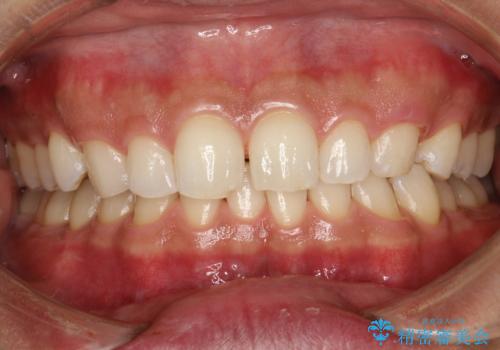

歯と歯の間の着色をPMTCでできる限り除去

- 歯と歯の間の着色を綺麗にしたいとのことで来院されました。PMTC60分で取れる範囲の着色や歯石などの除去を行いました。

毎日丁寧に歯磨きをしていても、日常生活での飲食物などにより着色してしまうことはあります。PMTCでは、歯の表面の凸凹にミネラルを補給して、ツルツルの表面に仕上げます